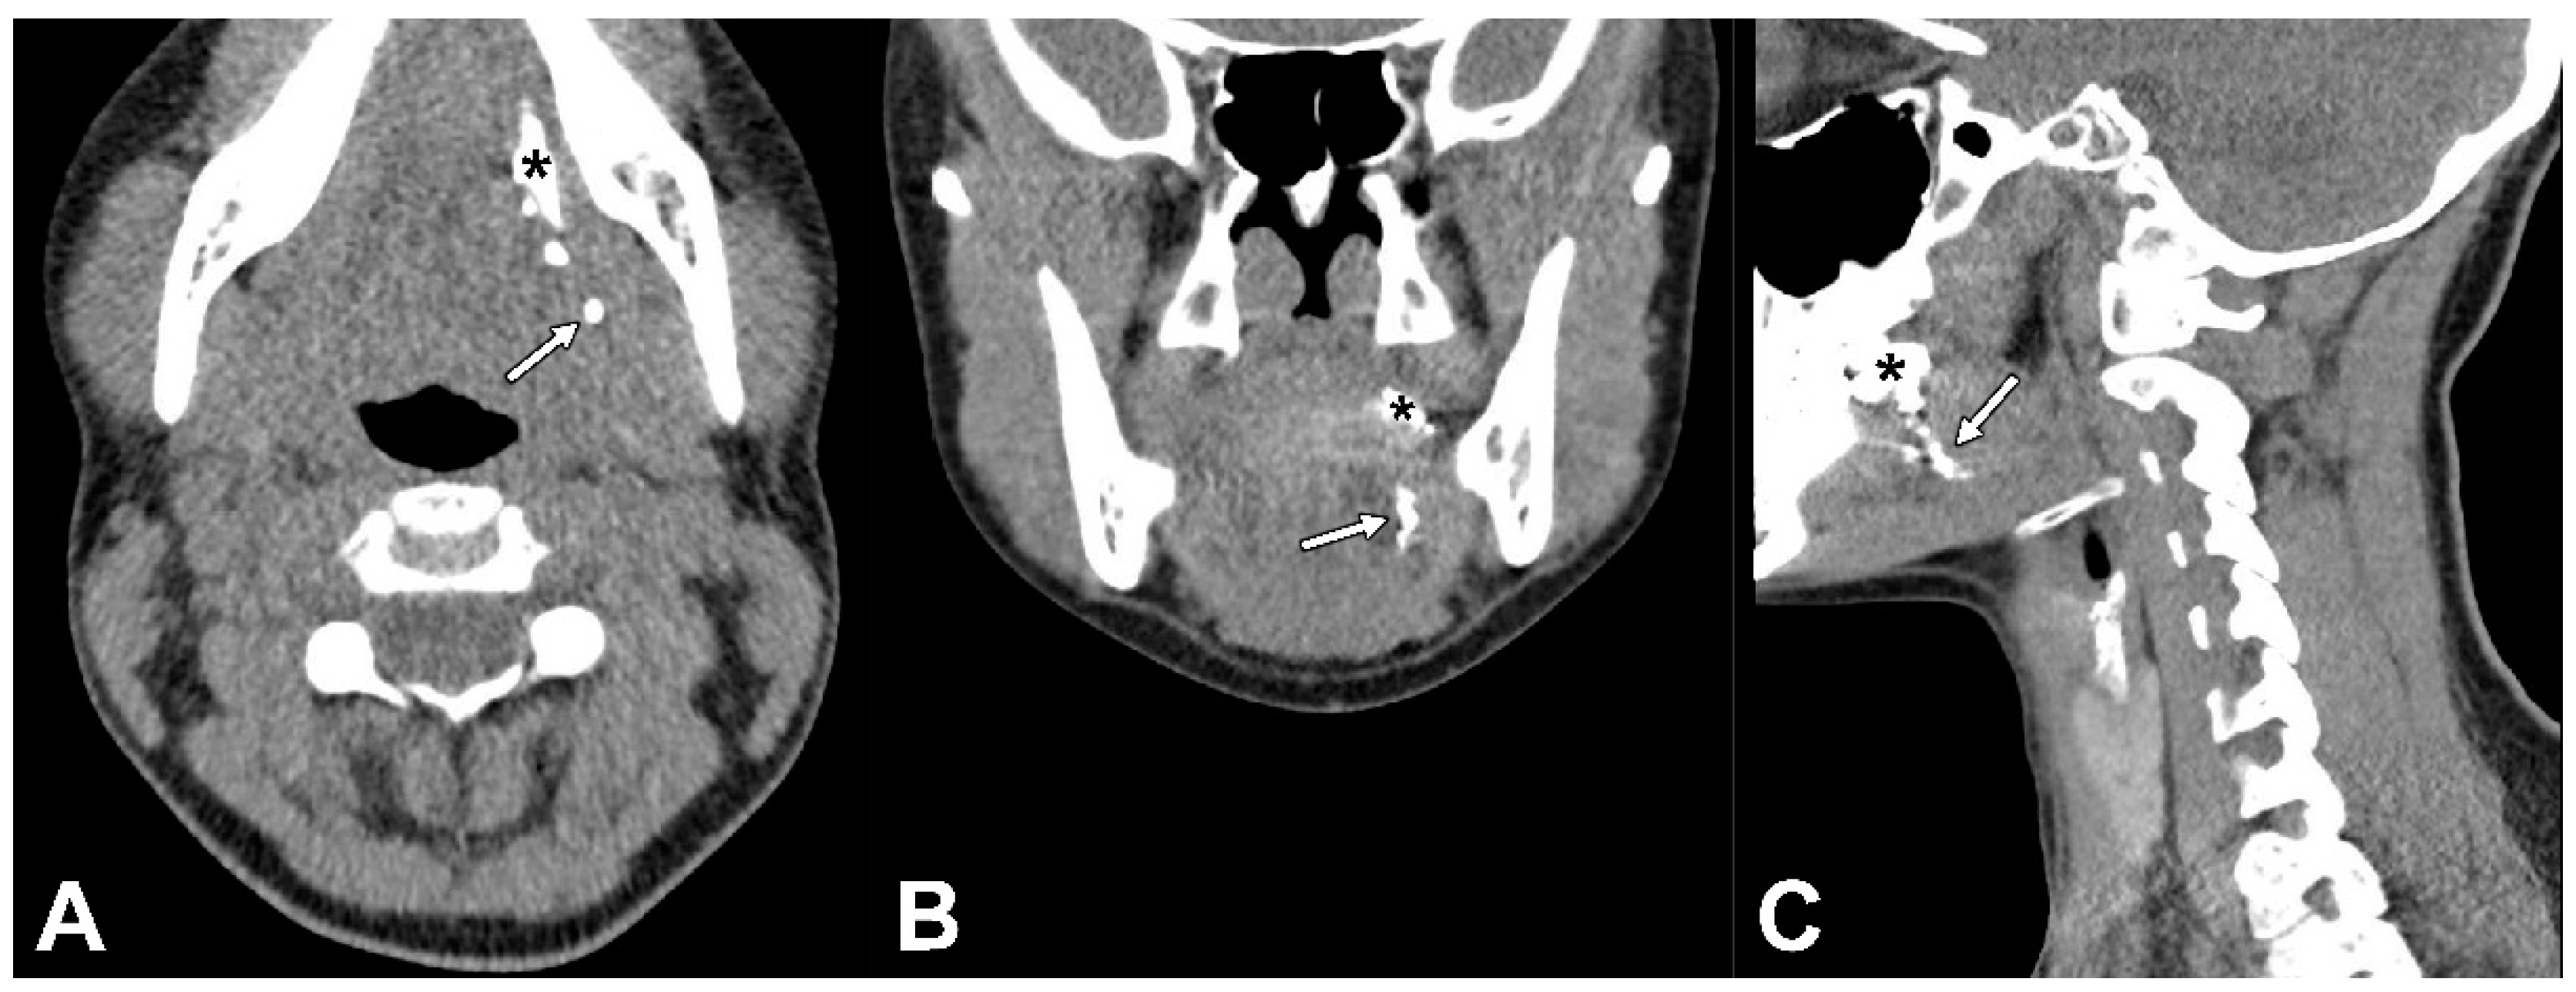

Figure 3.

CT lymphographic images acquired 25 min post-injection of Lipiodol® in the same patient (patient 6). (A) Axial plane, (B) coronal plane, and (C) sagittal plane; (*) injection site. Lymphatic drainage was observed (white arrows), yet no SLNs were identified on CTL in this patient.